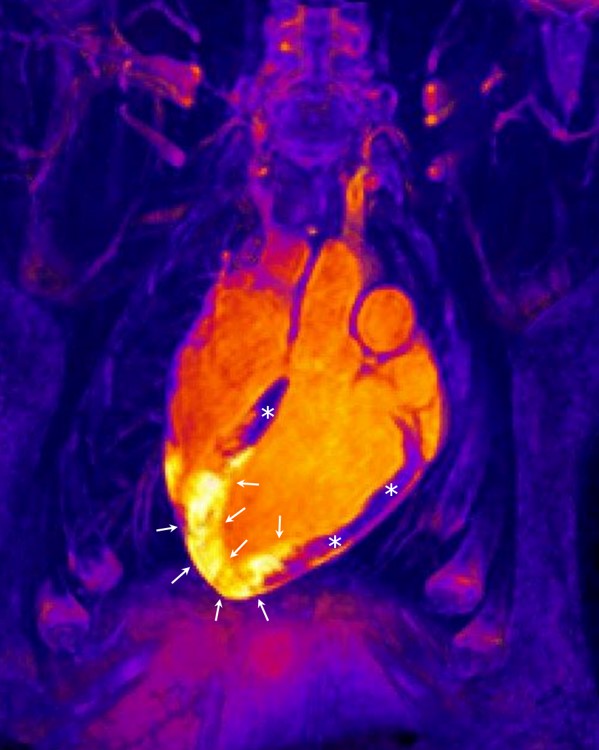

• CIBERONC

I Reunión del Programa de Tumores del Tracto Digestivo

18/10/2017